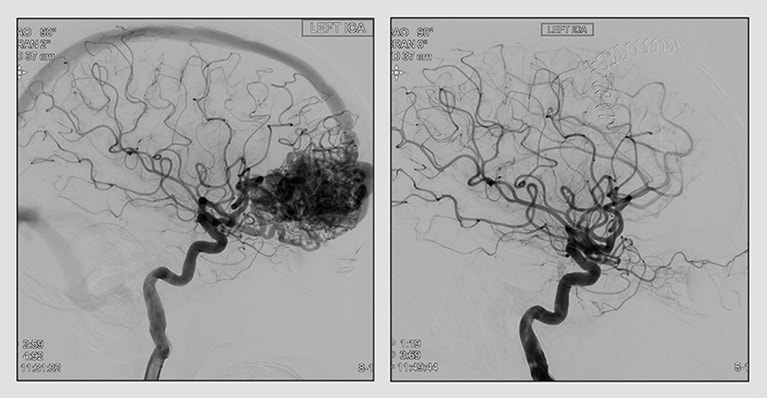

35. June 20, 2025

Proton SRS: A 'revolutionary' treatment for AVMs

Mayo Clinic uses proton stereotactic radiosurgery to manage arteriovenous malformations (AVMs). The technology precisely targets AVMs while sparing healthy tissue.